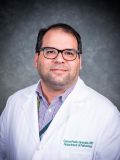

- Melanocytic nevi of the scalp (Am J Dermatopathol 2016;38:867):

- Melanocytes can be enlarged with irregular nuclei but atypia should be uniform throughout the nevus

- May contain large irregular nests in close proximity to one another

- Lentiginous growth may be prominent

- Pagetoid spread is a common feature

- Lesion can have broad junctional involvement and involve adnexa

- Single cell dispersion can be seen at lateral edges

- Lateral circumscription and maturation should be maintained, however symmetry may be lost (Am J Dermatopathol 2016;38:867)

- Prominent stromal fibrotic response can be seen